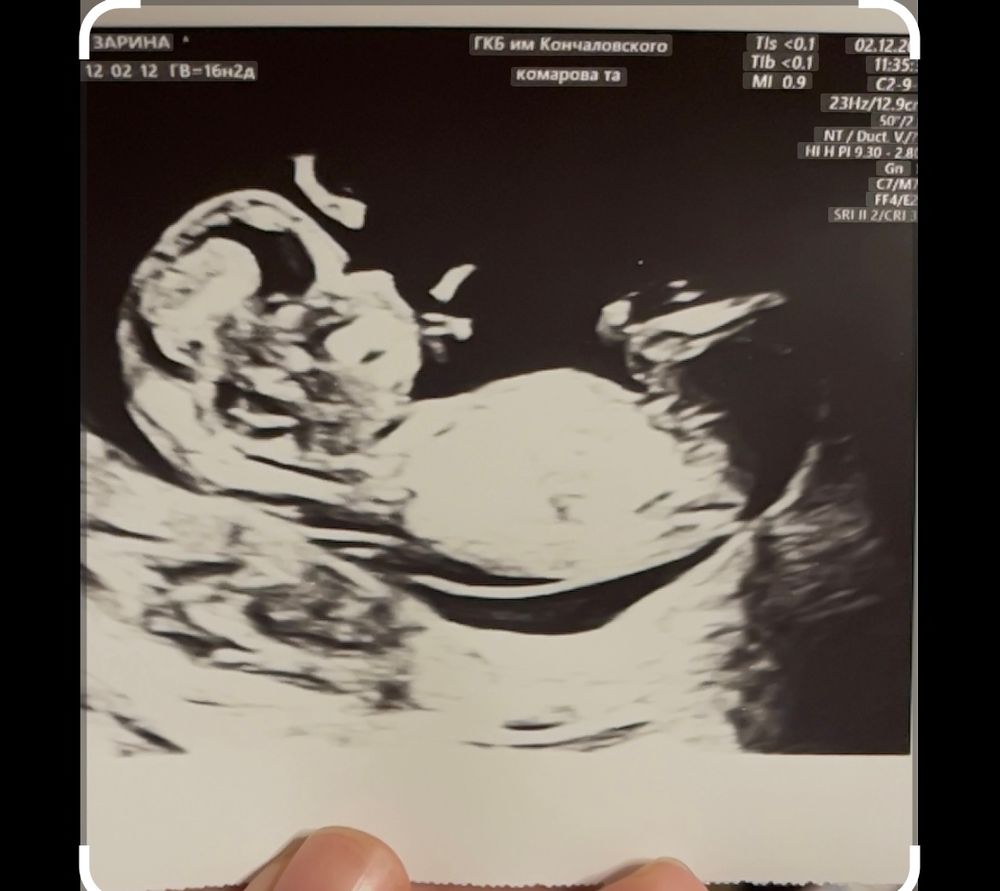

Девочки 17 недель МАЛЬЧИК 👦 Изображение

29.12.2024

Я девочку вижу! Напишите потом пожалуйста, права ли я была или ошибалась!